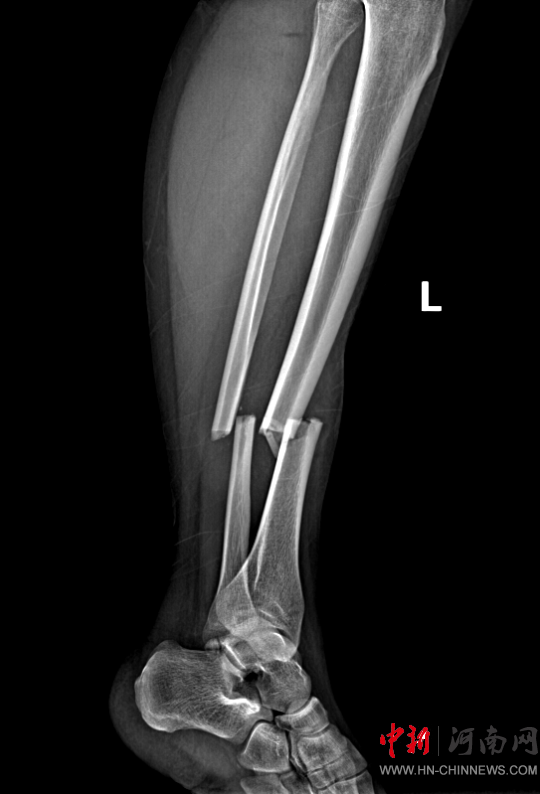

患者,女,32歲,車(chē)禍傷,到達(dá)確山縣人民醫(yī)院急診科創(chuàng)傷中心救治時(shí)血壓80/45mmHg,心率115次/分,處于昏迷、休克狀態(tài),病情危重。急診科迅速啟動(dòng)創(chuàng)傷中心急救綠色通道,醫(yī)護(hù)人員立即展開(kāi)搶救,積極抗休克治療的同時(shí),聯(lián)系神經(jīng)外科、胸外科、急診重癥監(jiān)護(hù)室緊急會(huì)診,同時(shí)快速CT、床旁FAST檢查明確診斷。通過(guò)一系列急救措施,患者的休克狀態(tài)稍微好轉(zhuǎn),經(jīng)多學(xué)科會(huì)診后明確診斷為:多處損傷并失血性休克、彌漫性軸索損傷、蛛網(wǎng)膜下腔出血、腦挫傷、股骨及脛腓骨粉碎性骨折、多發(fā)肋骨骨折并肺挫傷、腰椎骨折。ISS評(píng)分高達(dá)50分,死亡率極高,患者病情危重,立即送入急診重癥監(jiān)護(hù)室進(jìn)行高級(jí)生命支持治療。

患者病情好轉(zhuǎn)后,該院急診科主任岳春彥和創(chuàng)傷治療團(tuán)隊(duì)為患者制定了詳細(xì)的手術(shù)規(guī)劃,傷后第10日,患者在全身麻醉下進(jìn)行“左股骨粉碎骨折及脛骨粉碎骨折髓內(nèi)釘內(nèi)固定術(shù)+骨移植術(shù)、腓骨骨折復(fù)位內(nèi)固定術(shù)”,病情平穩(wěn)后轉(zhuǎn)入急診科病房治療,切口愈合后,患者轉(zhuǎn)入康復(fù)醫(yī)學(xué)科進(jìn)行腦功能康復(fù)和下肢關(guān)節(jié)康復(fù)治療。目前,患者能夠與人正常溝通交流,左下肢關(guān)節(jié)功能也恢復(fù)良好,已出院。